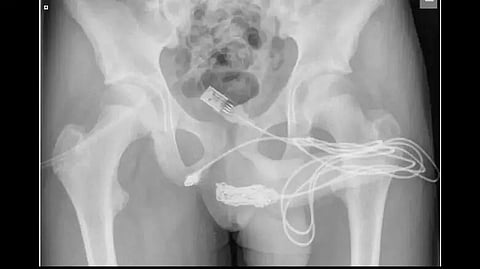

Doctors wrote in a Science Direct report, "The two distal ports of the USB wire were found to be protruding from the external urethral meatus whilst the middle part of the knotted wire remained within the urethra. The patient was an otherwise fit and healthy adolescent with no history of mental health disorders."

The tangle and number of knots in the cable reportedly made it impossible for doctors to cut it with a metal cutter, so they had to conduct an operation.

An insertion was made between his genitals and anus to allow access to the trapped cable, with catheters fitted for body waste removal.

Doctors explained, "Both ends of the wire were pulled out successfully through the external urethral meatus."